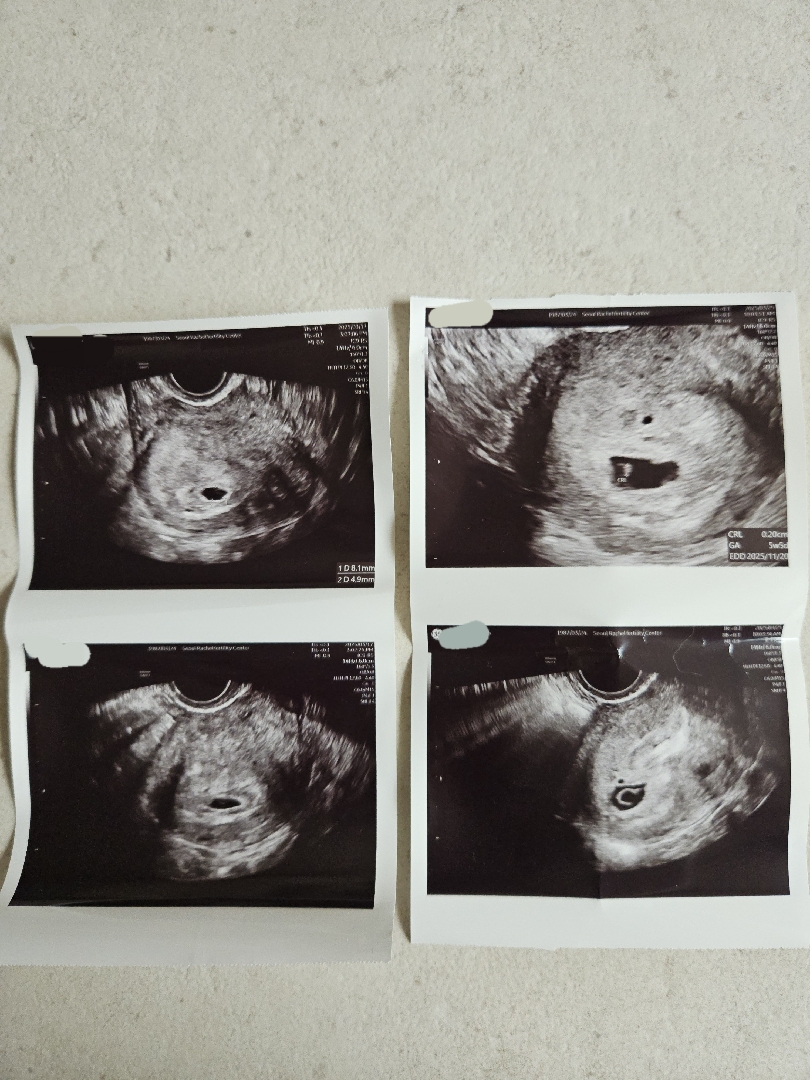

아까 6주5일차 인데 심장 안뛴다는 쓰니인데,

저도 같은상황이에요! 그래도 일주일 사이 난황도 예쁘게 만들어져서 보여주는거 보니 앞으로도 잘 자라줄것 같아 편안한 맘으로 일주일 더 기다리려구여ㅎㅎㅎㅎ 다음주에는 심장소리 꼭 들어요!!!

네네!! 아기는 강하다고 하니 믿어 볼게요!! 우리 함께 화이팅 해요!!